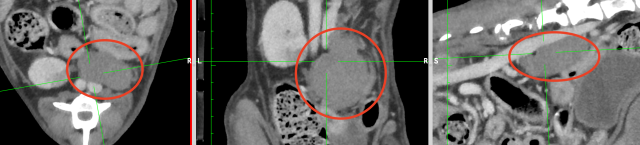

腹腔内停留精巣腫瘍のCT画像(赤丸)

・CT検査:がんの大きさや広がり、リンパ節転移、遠隔転移の評価

※CT検査は必須ではありませんが、腫瘍が大きい場合やお腹の中に腫瘍がある場合、レントゲン検査や超音波検査で転移が疑われる場合は必須の検査です。